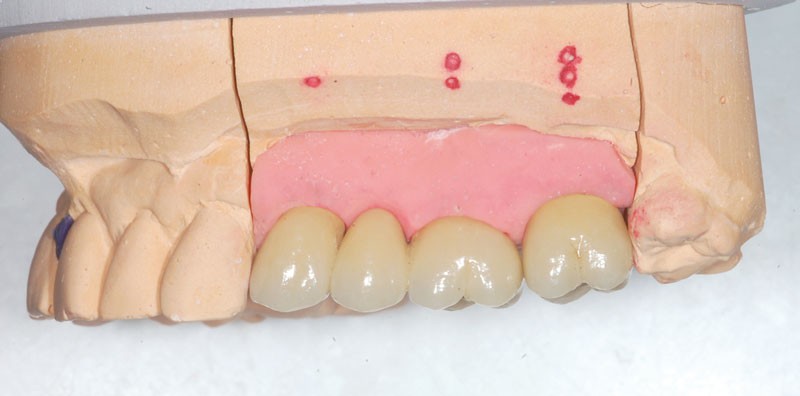

Le modèle de travail est fabriqué au laboratoire, des piliers CFAO Atlantis™ sont réalisés en fonction du bridge antagoniste transitoire.